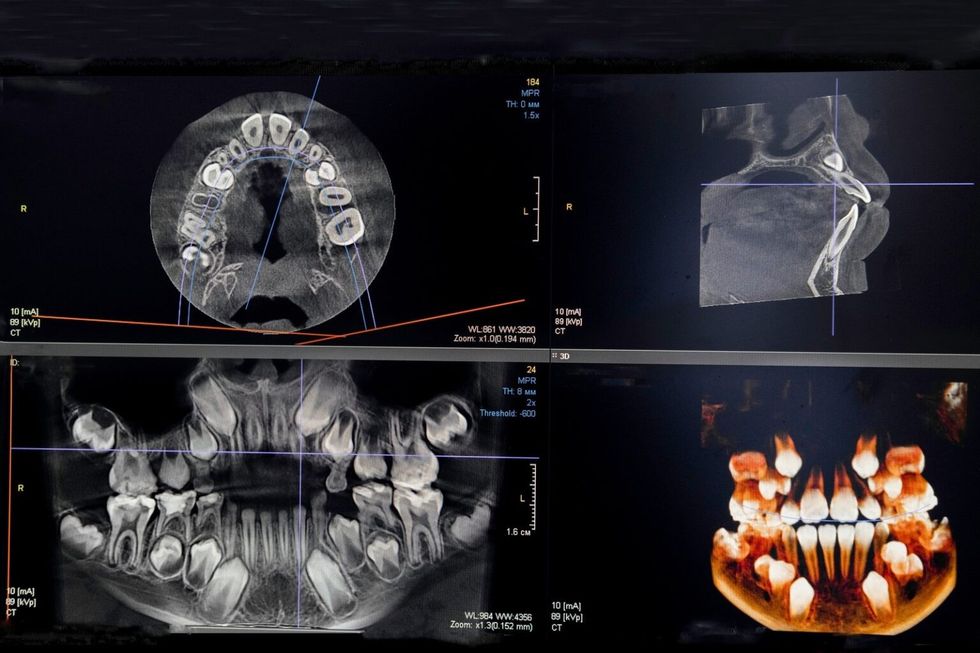

Nëse ndërhyrja implantologjike është e planifikuar mirë dhe ka përgatitje adekuate të pacientit, rreziku i komplikimeve reduktohet në minimum. Me masat e reja diagnostike moderne, të gjitha masat e rëndësishme anatomike të cilave duhet t’u kushtojmë vëmendje gjatë punës meren para kohe. Gjithashtu, imazhet CBCT të nofullës së sipërme dhe të poshtme na ofrojnë një plan të hershëm për pozicionin e saktë të implantit. Me ndihmën e stomatologjisë digjitale tashmë përcaktohet se ku do të vendoset implanti, gjatë së cilës krijohet një udhëzues implantologjik i individualizuar. Ky udhëzues synohet të fiksohet në nofullën e sipërme ose të poshtme, në varësi të vendit ku do të jetë vetë ndërhyrja dhe të ndihmojë në implantimin.